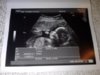

kaja, ależ cudnie się ułożyło!! parka! i faktycznie nie wyprą się, ze są rodzeństwem

gratulacje!!!!